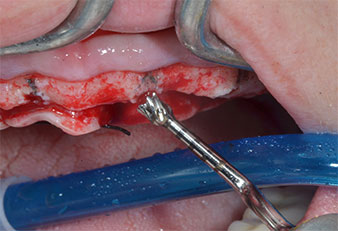

Implant stability

Fig. 7: Implant stability is determined with a SmartPeg and the W&H Osstell ISQ module. All values are in the medium to high range, with a minimum of ISQ 69.